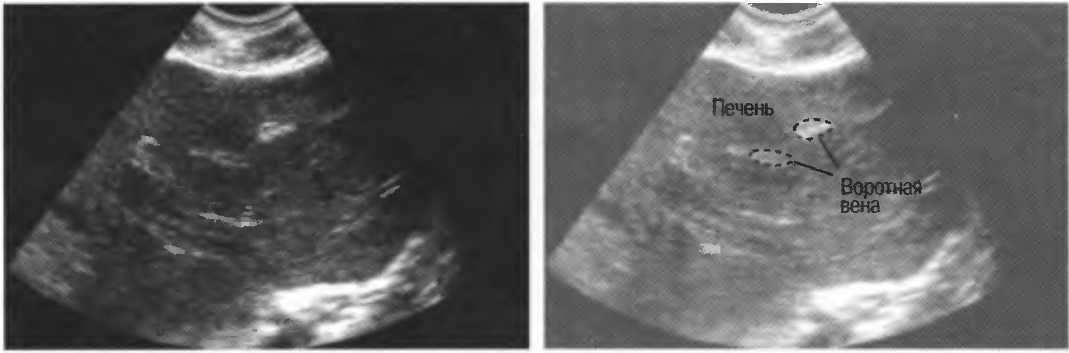

4. У здоровых обследуемых паренхима печени должна быть немного более эхогенна. чем кора рядом расположенной почки (рис. 26).

Рис.26. Продольный срез через печень и правую почку: нормальная паренхима печени более эхогенна, чем паренхима нормальной почки. Это еще один способ проверки качества изображения.